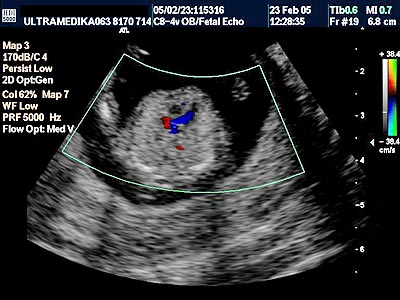

A) U ovoj starosti trudnoće se savetuje obavezna procena građe srca ploda iz sledećih razloga:

a. Srce je završilo svoj razvoj do 11. nedelje trudnoće.

b. Učestalost srčanih mana ploda je šest puta češće nego hromozomskih anomalija.

c. Amniocenteza i testovi iz krvi trudnice ne otkrivaju urođene srčane mane.

d. Ako je registrovana krupna srčna mana ploda savetuje se prekid trudnoće u dozvoljivom terminu prekida tj u I trimestru trudnoće

e. U daljem toku trudnoće u II ili III trimestru pregled srca ploda ne mora uvek biti optimalan. Na ovo utiče sigurno nepovoljan položaj ploda, posteljica na prednjem zidu, manjak plodove vode, konstitucija trudnice itd.

Procena srca se ogleda u proceni položaja srca, proceni anatomskih karakteristika sve 4 srčane šupljine tj. određivanje njihovog adekvatnog položaja, proceni položaja AV valvula, proceni postojanja AV kanala, adekvatnom položaju aorte i plućne arterije, i odnos velikih krvnih sudova na odgovarajućim presecima tj. 3VV i 3 VT. Često je i venska drenaža dostupna pregledu. Procena toka krvi je moguća aparatima koji mogu kodirati oskudan protok kroz srce u ovoj gestacionoj starosti. Adekvatno prikazivanje prolaska krvi kroz srce nije moguć bez postojanja Broad band CD i kolor Power Dopplera.